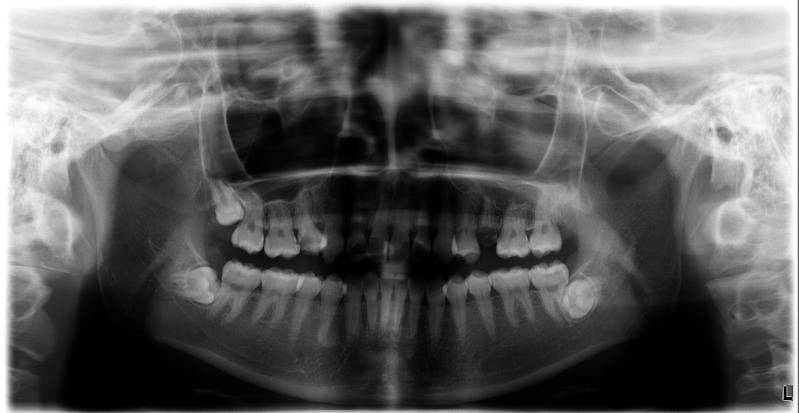

我现在也在长智齿,我一口牙几乎没有好牙了